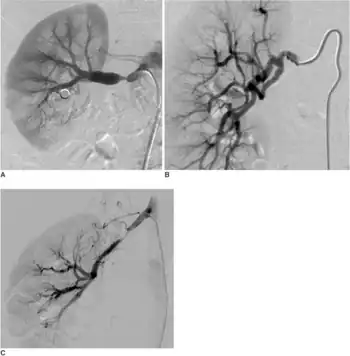

| The "string-of-beads" feature in multi-focal fibromuscular dysplasia. The sign is caused by areas of relative stenoses alternating with small aneurysms. | |

The second type, multi-focal fibroplasia, involves thickening of the media and collagen formation. It is typically reported as having the appearance of a ‘string of beads’ on angiographic review.[4] "The 'bead' component is often larger than the normal arterial lumen, and in a subset of patients with FMD, aneurysms are present that may require treatment."[4] The multi-focal subtype of FMD accounts for nearly 80% to 90% of all FMD cases.[4] (previously known as medial)